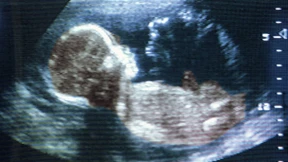

Ein Siebenjähriger liegt in einer Bochumer Klinik, der Tod fast unausweichlich, seine Haut wegen eines Gendefektes zerstört. Stammzellforscher sehen eine Chance: Sie retten ihn, indem sie dem Jungen eine runderneuerte Ersatzhaut züchten.